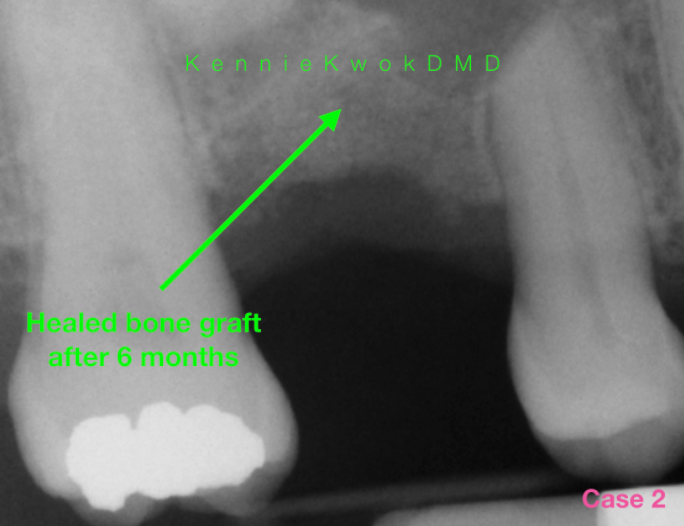

Are You Put to Sleep for a Dental Bone Graft? Exploring the Benefits Can I Request To Be Put To Sleep For Dental Work Sedation, better known as sleep dentistry, is an effective approach for minimizing anxiety and discomfort during dental procedures. Learn how sedation dentistry can help you feel calm and comfortable during dental procedures. Learn about the different types of dental anesthetics, how they work, and what to expect before and after your procedure. General anaesthesia is rarely used for dental treatment. Can I Request To Be Put To Sleep For Dental Work.

Are You Put to Sleep for a Dental Bone Graft? Exploring the Benefits Can I Request To Be Put To Sleep For Dental Work Iv (intravenous) sedation is sometimes called ‘sleep dentistry.’ you won’t be put to sleep, but you’ll have reduced awareness and feel relaxed. Learn how sedation dentistry can help you relax during dental procedures, from minimal to general anesthesia. None of these techniques involve “being put to sleep” or losing consciousness, even though advertisements for “sleep dentistry” sometimes refer to iv. Can I Request To Be Put To Sleep For Dental Work.

Are You Put to Sleep for a Dental Bone Graft? Exploring the Benefits Can I Request To Be Put To Sleep For Dental Work Sedation, better known as sleep dentistry, is an effective approach for minimizing anxiety and discomfort during dental procedures. Learn about the different types of dental anesthetics, how they work, and what to expect before and after your procedure. Learn how sedation dentistry can help you feel calm and comfortable during dental procedures. Can i be put to sleep for dental. Can I Request To Be Put To Sleep For Dental Work.

Are You Put to Sleep for a Dental Bone Graft? Exploring the Benefits Can I Request To Be Put To Sleep For Dental Work General anaesthesia is rarely used for dental treatment nowadays. Learn about the different types of dental anesthetics, how they work, and what to expect before and after your procedure. Iv (intravenous) sedation is sometimes called ‘sleep dentistry.’ you won’t be put to sleep, but you’ll have reduced awareness and feel relaxed. Can i be put to sleep for dental treatment?. Can I Request To Be Put To Sleep For Dental Work.